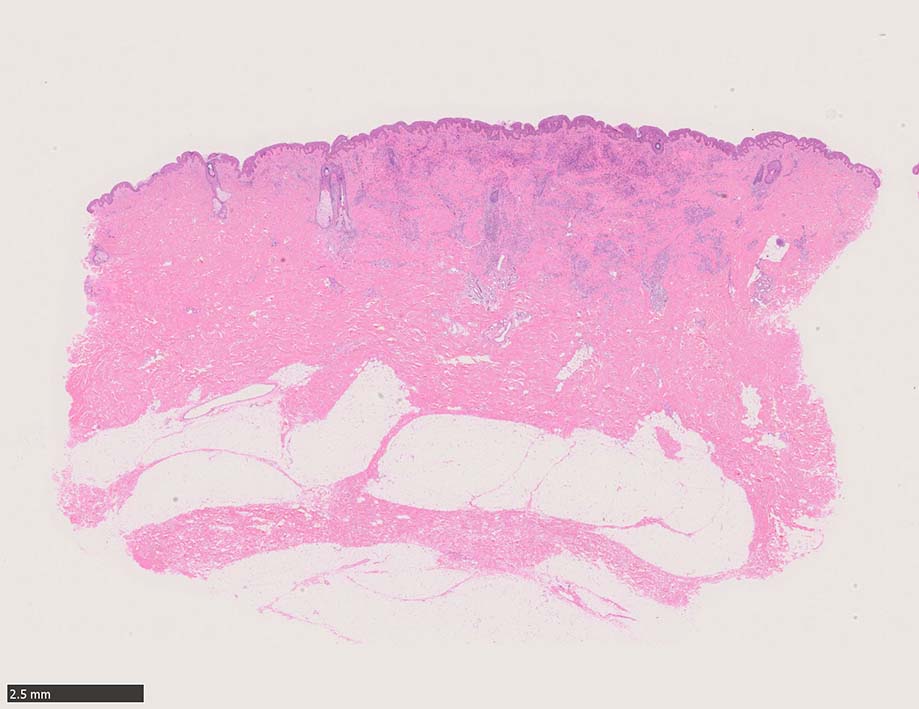

肉眼で平坦な斑状(macule)病変 --> 平板にやや盛り上がった隆起; 局面(plaque)病変 --> 更に進行し結節状(nodule)病変に進行する. (病理所見も病変の進行とともに変化している.)

初期斑状病変の病理

初期の斑状病変の組織学的所見はごく軽度の炎症反応の様相を呈し, 真皮内の正常毛細血管を囲むようにして拡張した血管内皮様細胞による管腔が認められる.

好中球などの炎症細胞浸潤はまれであるが, 形質細胞はしばしば増加している.*5

この時点ではKaposi肉腫特有の線維芽細胞様紡錘形細胞(spindle cells)は少なく, 診断はときに困難である. (HHV-8免疫染色が必須)

局面状病変の病理

病変は真皮から皮下脂肪織に及ぶようになり, 血管内皮様細胞による新生管腔の増加と拡張, 浮腫が著明になる. 赤血球漏出やヘモジデリン貪食細胞もめだつようになる.

膠原線維間に紡錘形細胞が増生してくる.

結節性病変の形成

紡錘形細胞が著しく増生し束状に走行する部分と, 内皮細胞様細胞による多数の小管腔構造が巣状にひろがり, 一見, 線維腫と血管腫が混在しているように見える. 一部の症例を除き, これらの増生細胞は異型性に乏しいことが多い.

細血管周囲に血管内皮様の紡錘形細胞が増生, 一部に赤血球をいれた裂隙の形成がある. 細胞の異型はみられず, mitosisの増多もない. hemosiderin-laden macrophageが散在する.

病変は真皮内に現局している. 初期斑状病変に相当すると考えられる. 本例では, 特徴とされる形質細胞浸潤増加はみられない.